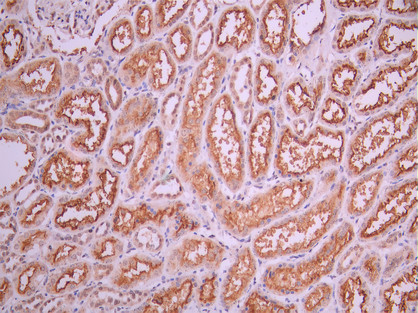

• IHC image of CSB-RA121260A0HU diluted at 1:100 and staining in paraffin-embedded human liver cancer performed on a Leica BondTM system. After dewaxing and hydration, antigen retrieval was mediated by high pressure in a citrate buffer (pH 6.0). Section was blocked with 10% normal goat serum 30min at RT. Then primary antibody (1% BSA) was incubated at 4°C overnight. The primary is detected by a Goat anti-rabbit polymer IgG labeled by HRP and visualized using 0.05% DAB.